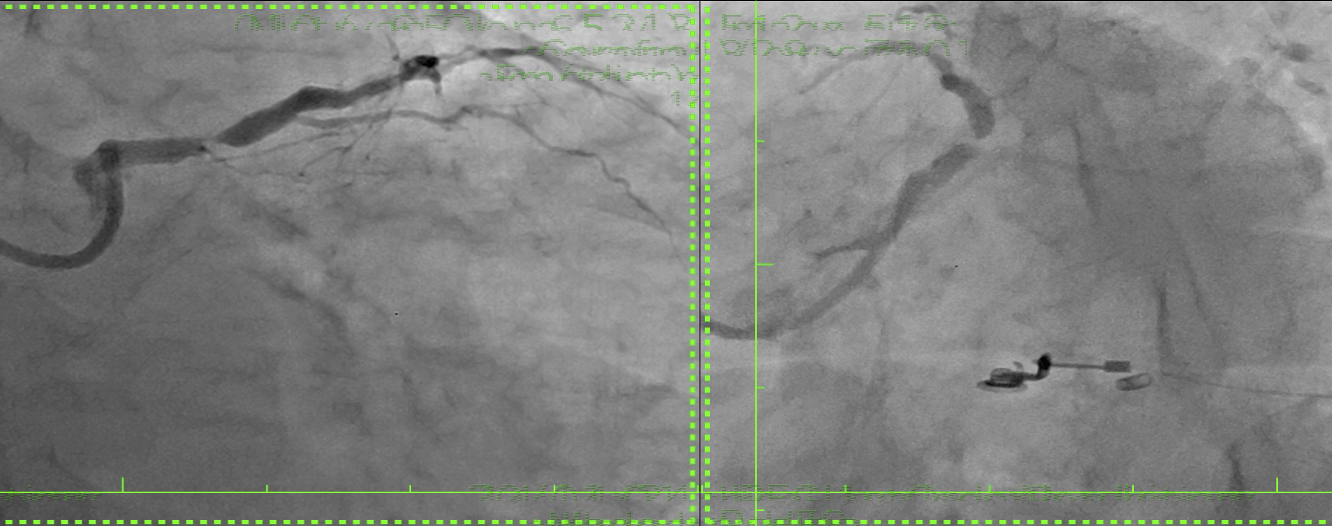

The procedure commenced with IABP insertion and the use of a 7F XB guiding catheter for an antegrade approach. A wire was advanced across the LM-LAD stenosis, and predilatation with a 2.5 mm semicompliant (SC) balloon revealed the faint ostium of the occluded LCx. A 45¡Æ angulated microcatheter facilitated the crossing of the LCx occlusion with a stiff wire, which was then exchanged for a standard workhorse wire.Following LCx predilatation, kissing balloon pre-dilation of the LM-LAD-LCx bifurcation was performed. A 3.0x18 mm Sirolimus stent was deployed in the proximal LAD. Subsequently, a 2.75x18 mm Sirolimus stent was placed in the LCx with minimal protrusion into the LM and crushed with a 3.5 mm non-compliant (NC) balloon. The crushed stent struts were recrossed, predilated with sequential SC balloons, and a distal optimization (DOT) was performed. A second kissing balloon inflation followed.A third Sirolimus stent (4.0x25 mm) was then overlapped with the previous stent in the LAD-LM segment. After a proximal optimization technique (POT) in the LM, the LCx was rewired. Final optimization included further DOT in both the LAD and LCx, a final triple kissing balloon inflation, and a concluding POT. An excellent final result was confirmed by IVUS (LAD area 9.2 mm©÷; LCx area 8.1 mm©÷; minimal lumen area 16 mm©÷) and angiography, after which the IABP was removed.

A 65-year-old woman with complex coronary disease, including distal left main stenosis and a chronic occluded LCx ostium, successfully underwent percutaneous intervention using a DK-crush stenting technique after refusing surgery. The challenging LCx origin, identified after LM-LAD predilatation, was crossed using a 45¡Æ angulated microcatheter. The patient remained asymptomatic with excellent therapy compliance at follow-up. The procedure's success was confirmed by IVUS, demonstrating the efficacy of tailored percutaneous approaches for complex lesions.